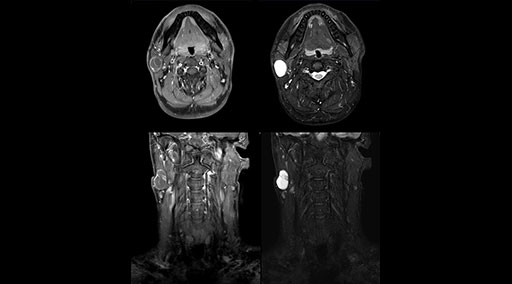

mDIXON TSE fat suppression helps DMG reduce repeats and supports diagnostic confidence

“Our DMG Lisle location includes a cancer center, so soft tissue neck scans, brachial plexus scans, and prostate scans are common. For these exams, mDIXON TSE provides excellent images with and without fat suppression all while helping us reduce repeats and work more efficiently,” Mr. Duffy says.

“With the 2-echo Philips mDIXON TSE the timing is short and the fatsat is very robust. The biggest thing is that you know your fat suppression will be good, even in thin patients or large patients that are off-center,” Mr. Sybesma says.

“Since we work in fixed time slots, not having to repeat scans is key for us,” Mr. Duffy adds. “With mDIXON TSE we get high quality results the first time – unless of course the patient absolutely jumps off the table. For us, that’s significant, because just a single repeat scan could put us behind schedule.

“mDIXON TSE raises our diagnostic confidence with its homogeneous

fat suppression. Neck exams and rheumatology patients are two examples where mDIXON TSE is especially useful,” Dr. Kaakaji says. “For us it’s also an efficiency boost in exams where we need pre and post T1-weighted images with great fat suppression.”